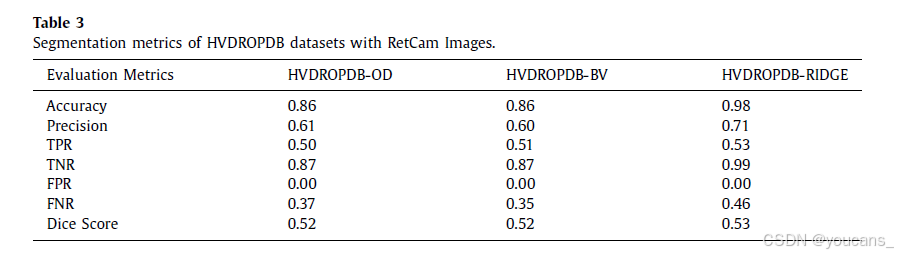

使用 AG U-Net 方法[7] 对 Neo 和 RetCam 图像进行分割。对 HVDROPDB 数据集进行分割的性能指标如表2 和表3 所示。

所有数据集都以 70:10:20 的比例划分为训练集、验证集和测试集,随机状态的种子数为42。